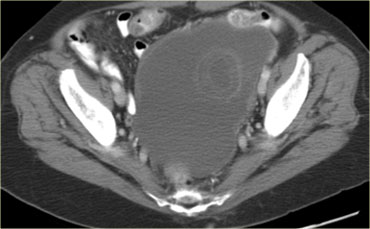

CT của cùng bệnh nhân xác nhận các tổn thương đặc-nang phức tạp hai bên kích thước lớn, phồng vào ổ bụng.

Mục đích của CT không phải là xác nhận những gì đã biết từ siêu âm, mà là để phân giai đoạn bệnh.

Dựa trên CT (hoặc MRI), không thể xác định loại mô học của khối u.

Điều này không có ý nghĩa quyết định. Bệnh nhân này sẽ được phẫu thuật.

Đối với các u biểu mô – nhóm u ác tính buồng trứng thường gặp nhất – ngay cả sau phẫu thuật, phân loại mô học chính xác của khối u ít quan trọng hơn nhiều đối với tiên lượng so với các yếu tố như giai đoạn FIGO, độ biệt hóa khối u và mức độ thành công của phẫu thuật trong việc loại bỏ toàn bộ bệnh.

Đối với bệnh nhân này, các đặc điểm quan trọng được thể hiện trên hình bên trái.

Có một tổn thương cấy ghép phúc mạc.

Khối u đã được phẫu thuật cắt bỏ và kết quả giải phẫu bệnh cho thấy đây là ung thư biểu mô buồng trứng dạng nội mạc tử cung.